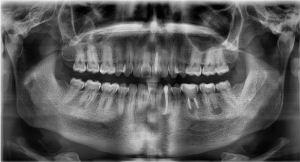

General clinical examinations displayed a rather short stature and frontal bossing. Intra-oral inspection revealed a poor general oral hygiene, with percussion pain at the lower left premolar (34) and second molar (37), but no pain sensation at the lower right second molar (47) (Figure 2a and 2b). Temperature and electric vitality tests elicited an adequate response at the lower right and left secondary molars (37-47). Radiographic examinations, including a panoramic view and cone beam CT-scan, showed periapical translucencies at the upper left central incisor, the lower left canine, the lower left primary and secondary molars and the lower right secondary molar (21-33-36-37-47) (Figure 2c). Moreover, it displayed enlarged pulp chambers and pulp horns, nearby the dentino-enamel junction.

Figure 2. Initial status of the patient. (a and b) Intraoral view of maxilla and mandible showing signs of dental crowding, but no apparent signs of caries. (c) Panoramic view from the first consultation.